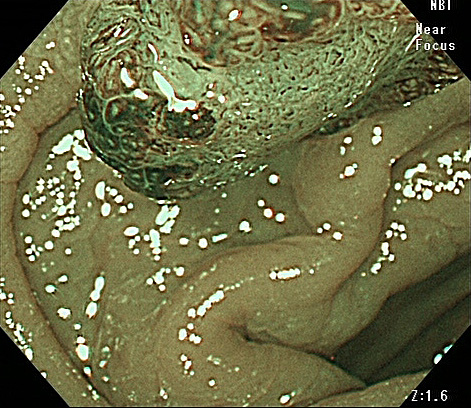

NBIモード

粘膜表層の毛細血管や微細構造が強調表示され病変の拾い上げに威力を発揮します。

従来から搭載されている機能ですが、従来品のNBIモードは画面が暗くなってしまうのが難点でした。「EVIS X1」ではNBIモードでの観察でも鮮明な画像が得られるようになりました。

腫瘍性病変を顕微鏡のように拡大して観察すると粘膜表面の微細な血管や構造が捉えられ病変の状態が分かります。

通常の内視鏡では見えません。

良性なのか、悪性なのか、良性であれば悪性化の危険性はどの程度なのか、悪性であれば内視鏡で切除が可能な早期病変なのかどうか、などが判断できます。

NBI拡大観察

10mmちょっとのそれほど大きくないポリープです。ポリープを取るだけなら内視鏡切除は容易でしょう。

ところが拡大観察により外科的切除が必要と判断しました。

腹腔鏡で腸管を切除するとすでにリンパ節転移がありました。リンパ節転移は外科的な腸切除が必要な“進行がん”です。

再発なく経過中です。